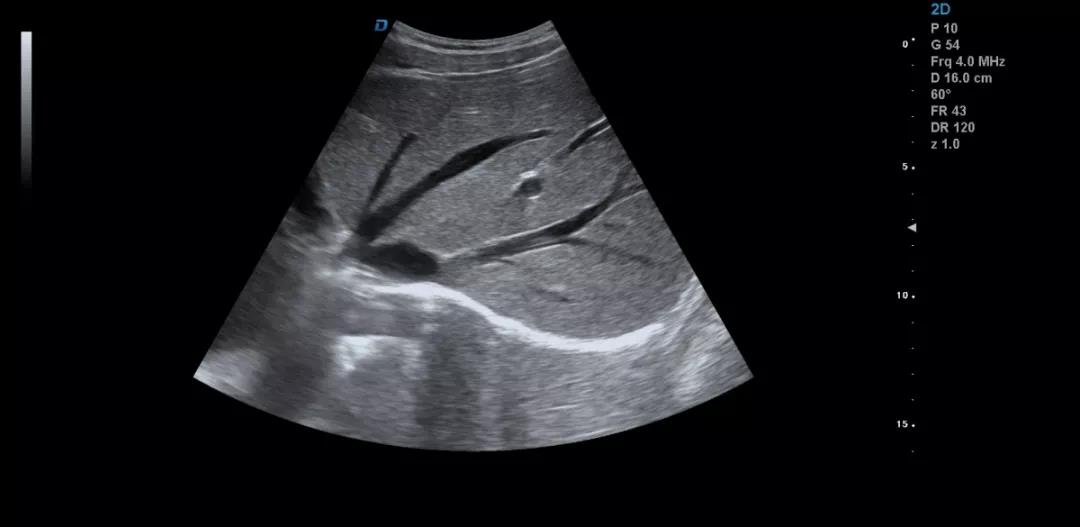

眾所周知,肝臟有很多檢查死角,成為超聲檢查的盲區(qū),如肺和骨所掩蓋處,肝右前上段及右后上段的膈頂部,左外葉外側(cè)角區(qū),沿肝臟表面的肋骨下區(qū)等等部位,只有極其細(xì)致的檢查配上精巧的手法才能盡可能的顯示清楚這些部位。

如果我們能夠細(xì)致的檢查每個病人,所謂的肝臟死角能夠盡可能的探測到,肝臟的死角其實只有膈頂部,其他的部位如果能細(xì)致檢查都可以探測到。

肝左葉掃查時,矚患者深吸氣,可以盡量使肝下移,更接近體表,顯示清楚,掃查至外側(cè)角肝臟消失的位置。然后探頭連續(xù)滑動,沿肋緣下斜切,矚患者深吸氣,探頭做扇形掃查,盡可能側(cè)動探頭至與皮膚平行,肝臟的絕大部分病變不會被遺漏。

對于肥胖體型或腹腔臟器明顯的,這種方法就不合適,可以采取肋間斜切的方法,自下而上逐個肋間連續(xù)掃查,注意不要做跳躍式掃查,這樣容易眼花也容易遺漏病變。

肝臟膈頂部掃查體會:

1)一般是讓患者深吸氣,讓肝臟下移,然后探頭盡量上翹;

2)當(dāng)然很多患者因肥胖或肺氣的干擾會顯示更差,這時我就讓患者深呼氣,把氣全部吐干凈,然后屏氣掃查;

3)還有就是不要沿著肋間隙掃查,而是和肋間隙成一定的角度緩慢向右上方腋前線掃查;

4)在平臥位掃查時,在橫切腎臟時探頭盡量上翹,甚至與腹壁平行,當(dāng)然在右側(cè)肋緣下也行;

5)變換體位掃查,肝臟因重力作用產(chǎn)生移位。左側(cè)臥位、右側(cè)臥位、各種斜位、還有站立位等等。

掃查肝臟時要配合患者的呼吸運動,采取你動我靜,你靜我動的掃查方法,并最大限度的側(cè)動探頭,最大角度的顯示肝臟。

發(fā)現(xiàn)肝臟病變時要多切面多角度掃查,可以了解病變的解剖位置并排除假陽性。